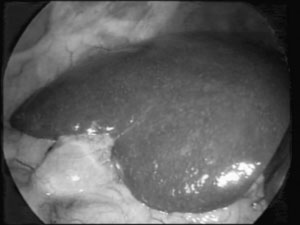

O fundo da vesícula é "laçado" com o

vesícula (Figuras 3 e 4).

| Figura 3 - Aspecto inicial da cavidade abdominal, mostrando o fígado, vesícula biliar e o omento, antes da tração pelo "Lap-loop". |